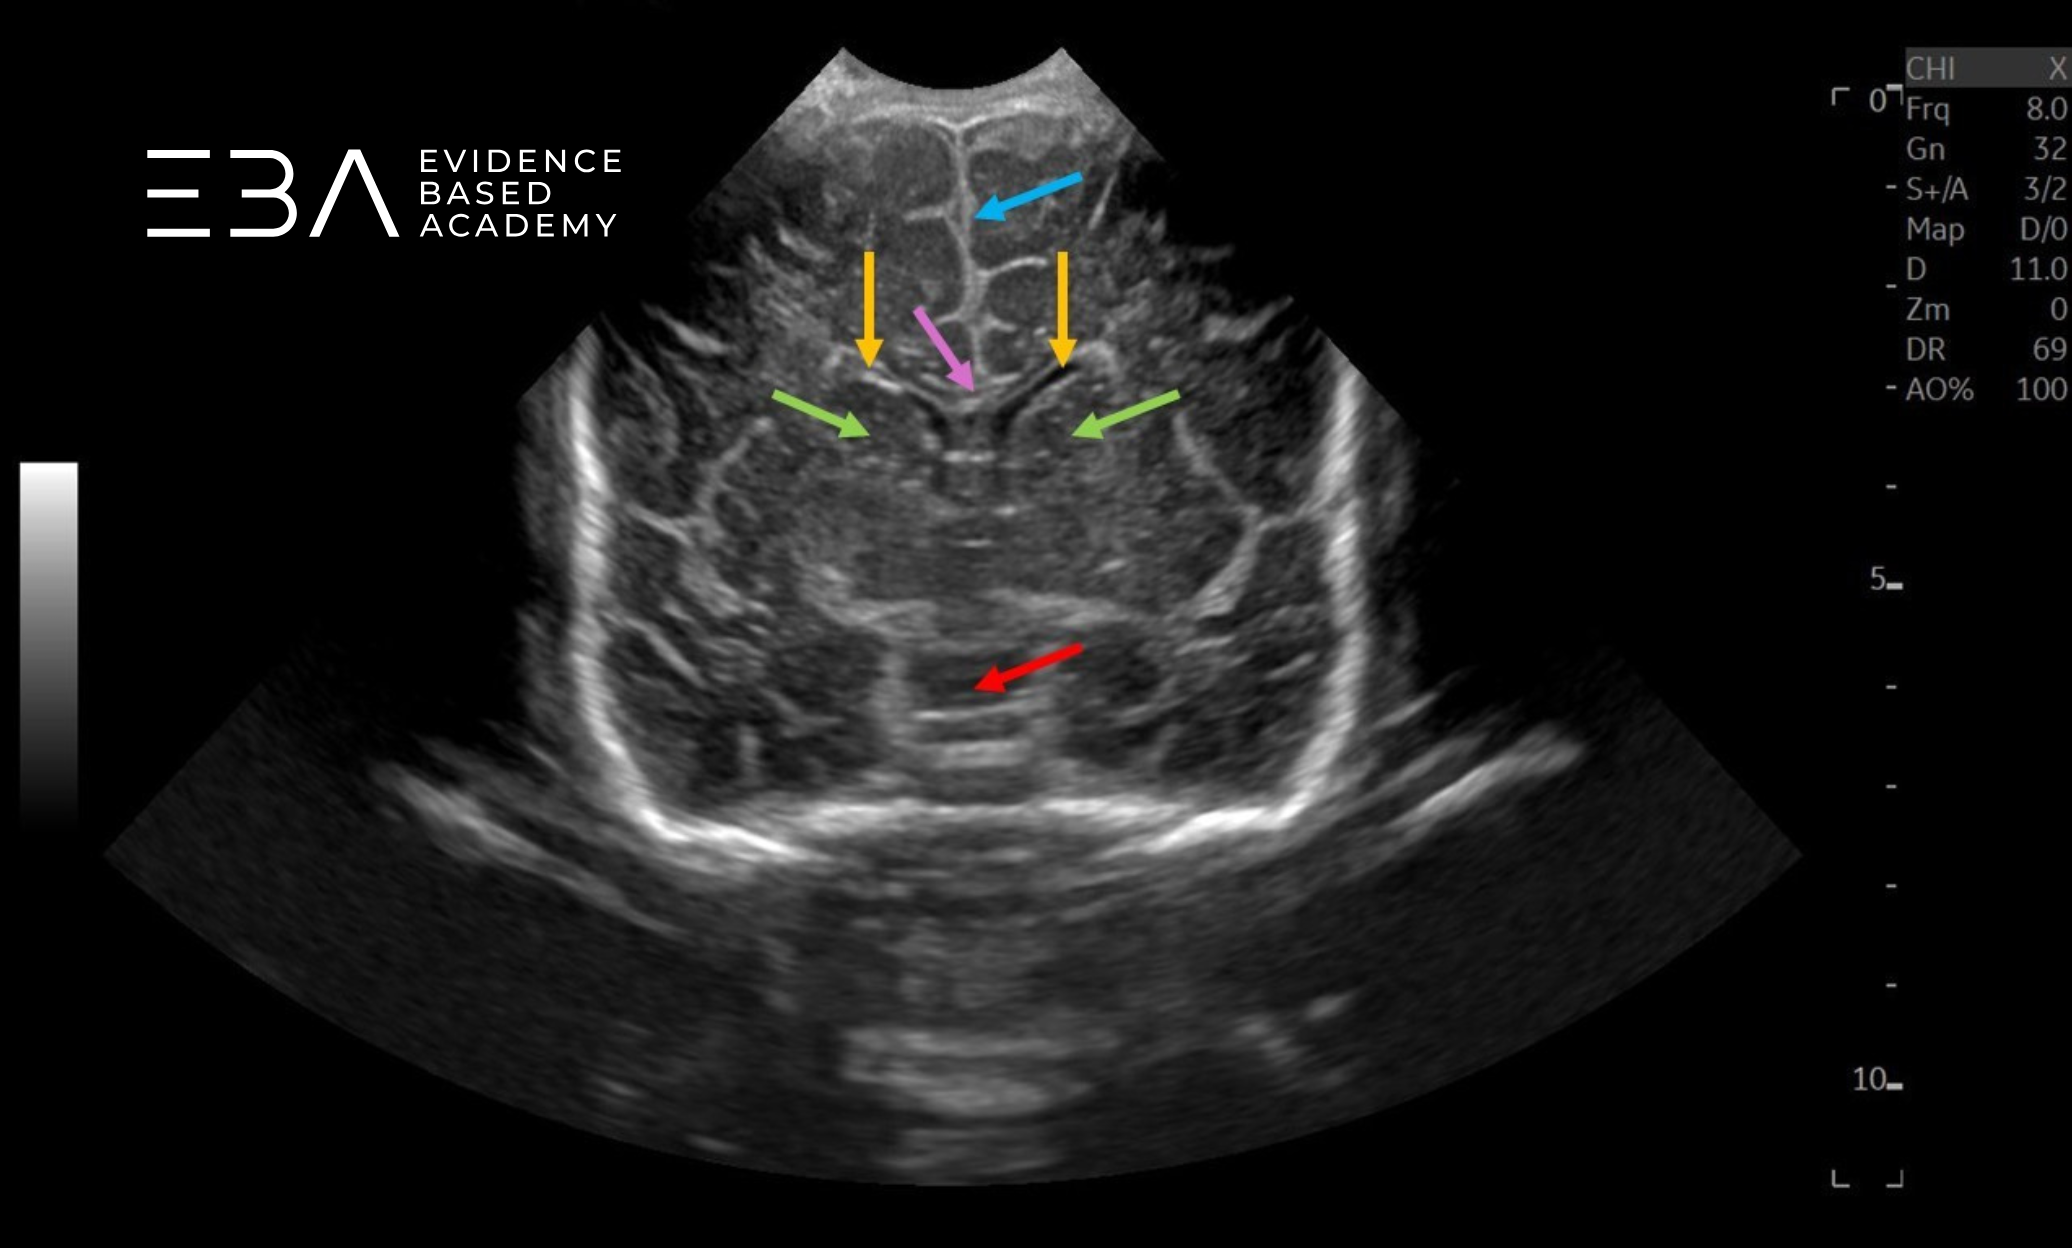

Badanie przez ciemiączko sutkowe

Obrazowanie przez ciemiączko sutkowe pozwala ocenić blaszki móżdżku, zbiornik wielki i komorę czwartą pod kątem prawidłowego wyglądu i wymiarów (6). Widoczne są również niektóre struktury nadnamiotowe, w tym tylna część układu komorowego, niekiedy komora trzecia, a także wzgórze, konary mózgu i zbiorniki podstawy mózgu (2). U wcześniaków przez to okno możemy dobrze uwidocznić również przeciwległą półkulę móżdżku (3).

zdj. 22

Głowica liniowa – badanie przez ciemiączko tylno-boczne. Półkula móżdżku (żółta strzałka), komora czwarta (czerwona strzałka).